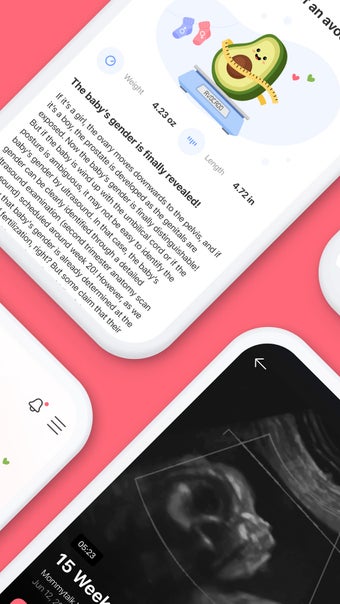

Momitalk adalah aplikasi yang dirancang untuk mendukung perjalanan kehamilan Anda dengan berbagai fitur canggih. Aplikasi ini memungkinkan pengguna untuk berbagi momen penting seperti detak jantung bayi dan gerakan pertama, serta mengakses video ultrasound kapan saja. Dengan begitu, Anda tidak perlu menunggu janji dokter untuk merasakan keajaiban tersebut. Momitalk juga memberikan informasi penting tentang perkembangan bayi dan perubahan tubuh selama kehamilan, serta memberikan panduan tentang tes prenatal yang perlu dilakukan.